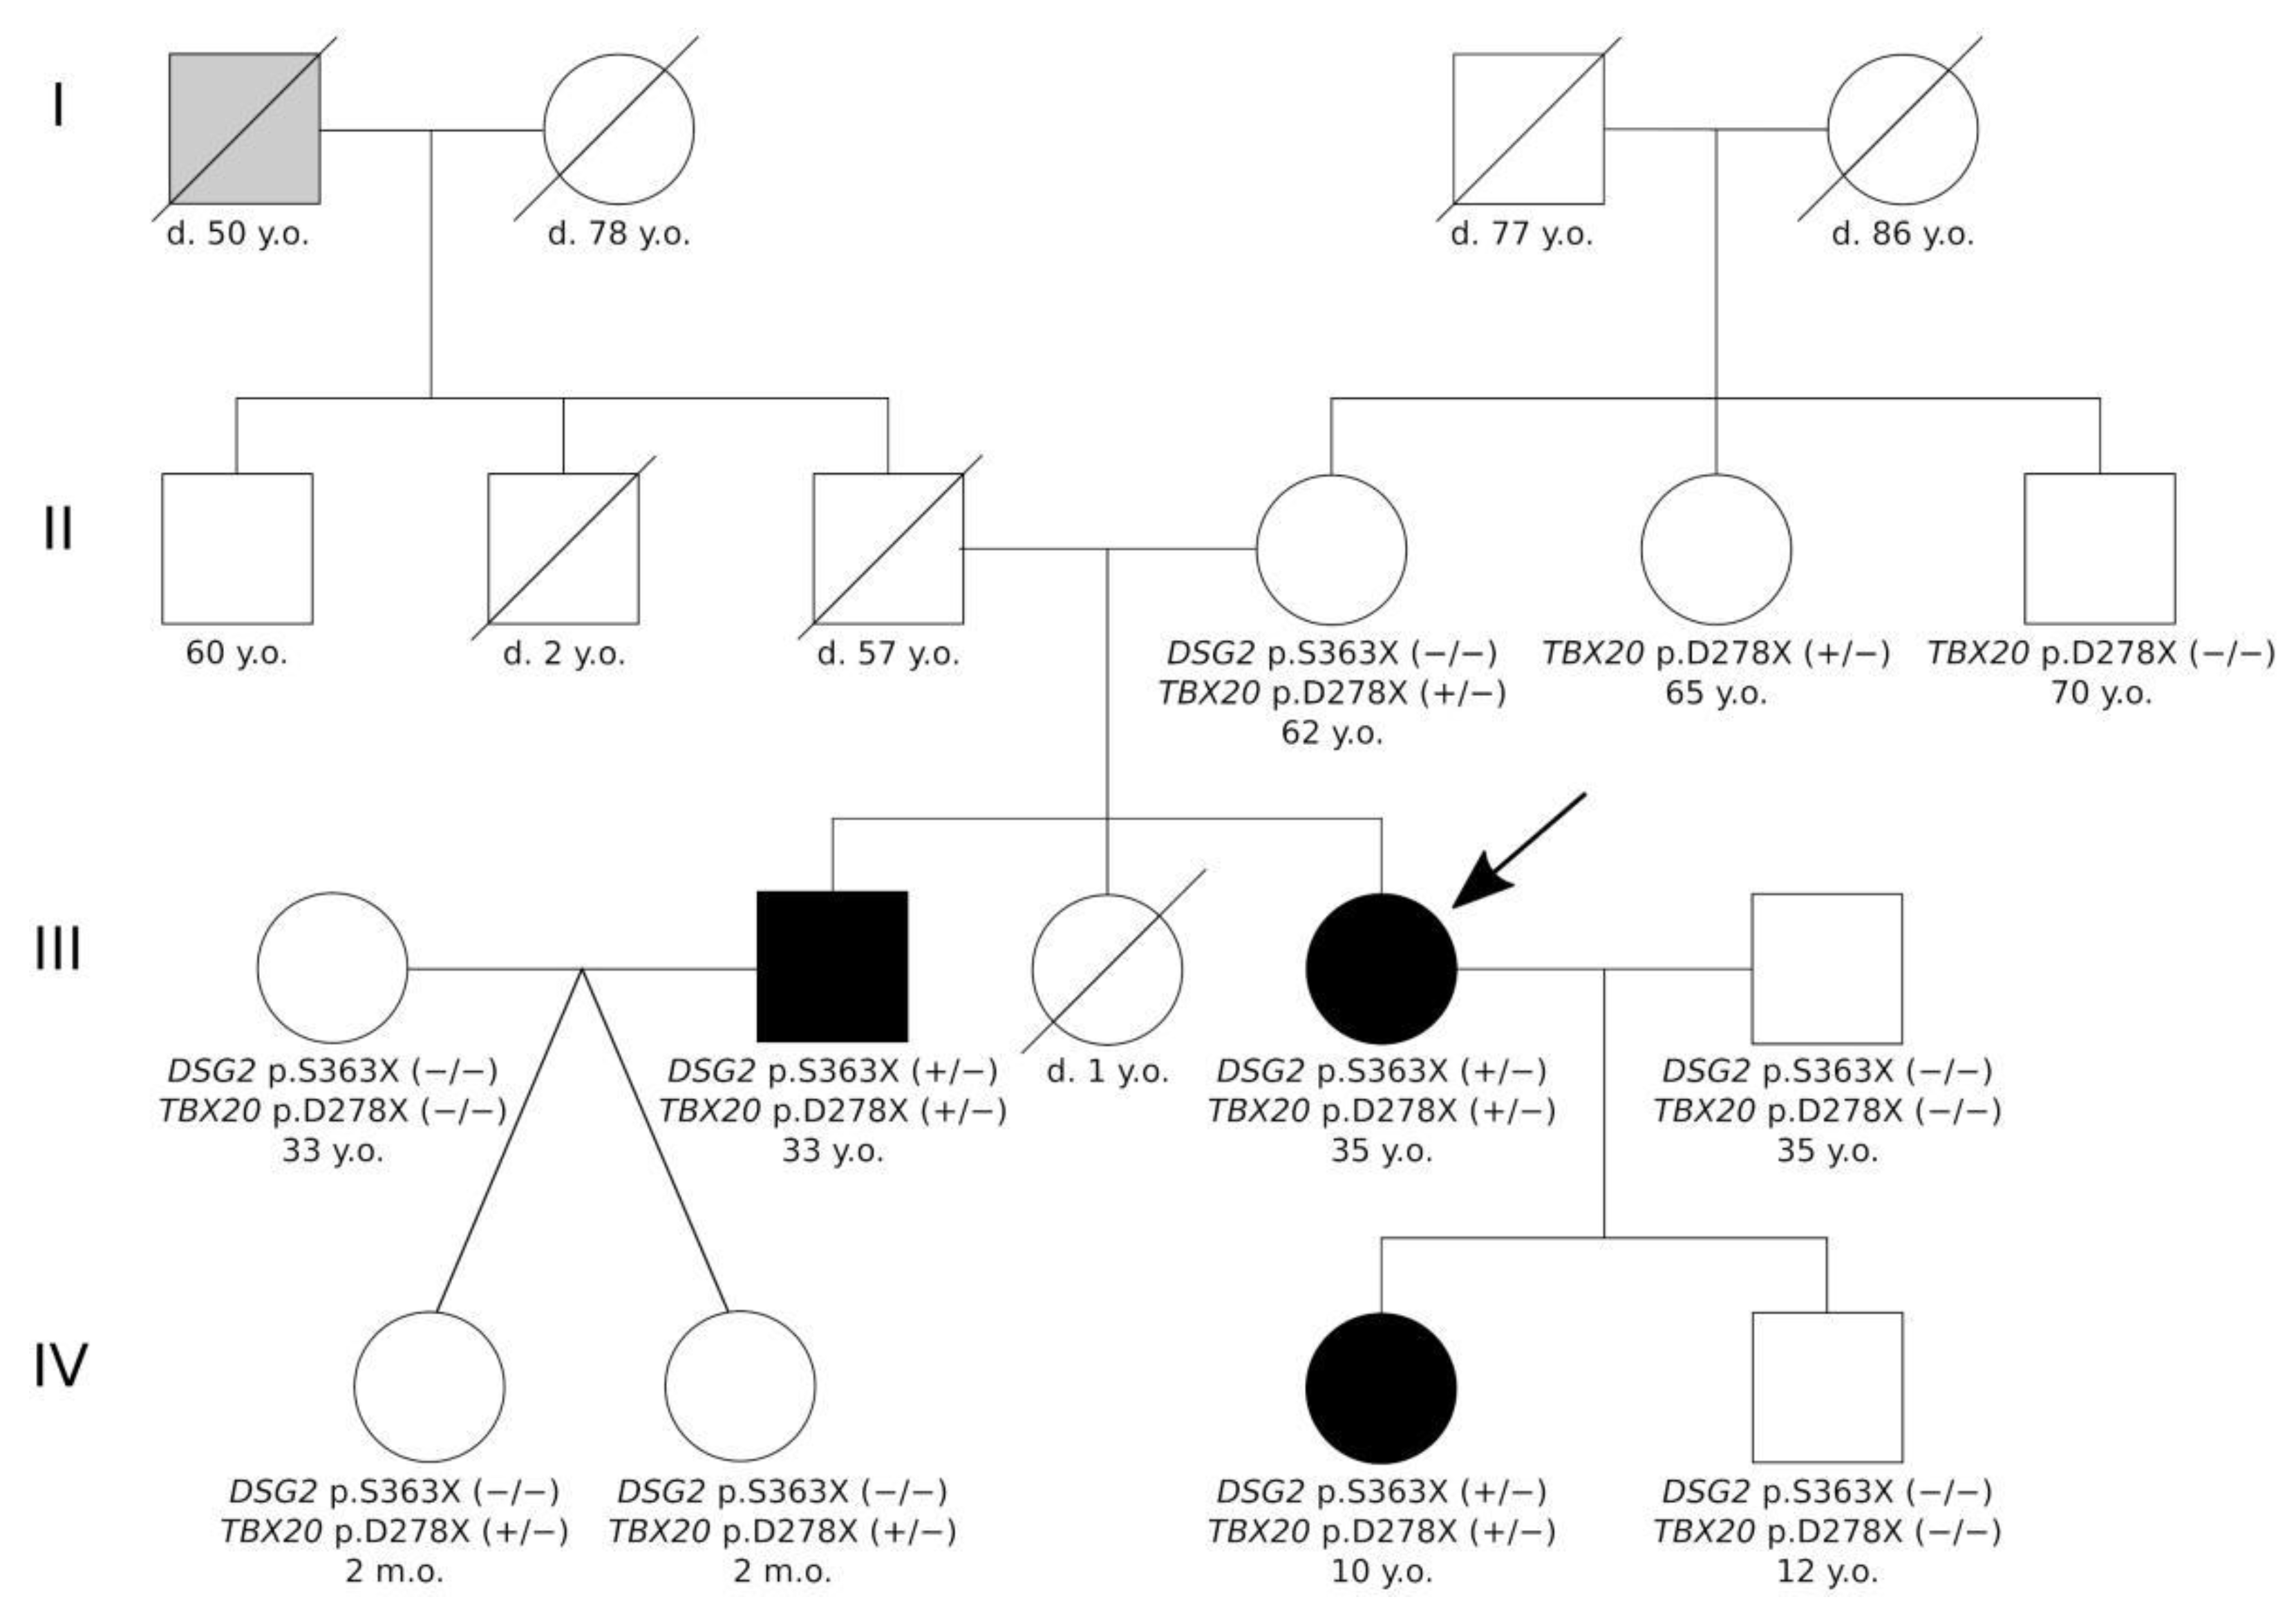

2. Results

2.2. Genetic Analysis

4.1. Clinical Description of the Patients